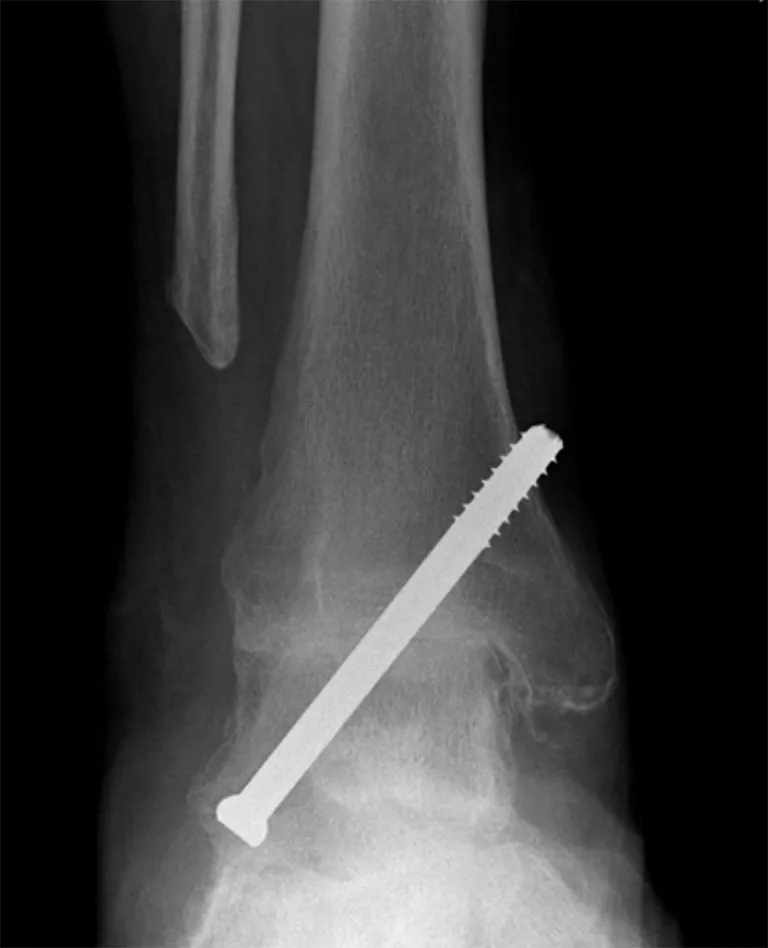

3. Ankle Fusion

(Also called Ankle arthrodesis)

What it is:

The damaged joint surfaces are removed and the ankle bones (tibia and talus) are fused together with screws or plates, eliminating motion at the joint. This relieves pain by stopping bone-on-bone movement.

Arthroscopic Arthrodesis:

This is the procedure I perform most commonly for ankle arthritis. It is performed with key-hole techniques, through 3 small incisions. The arthritic joint surfaces are removed using arthroscopic burrs and the joint fixed together with titanium screws. The operation takes approximately 1.5 hours. See Arthroscopic Ankle fusion.